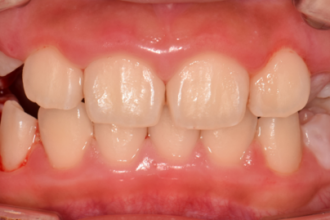

치아교정